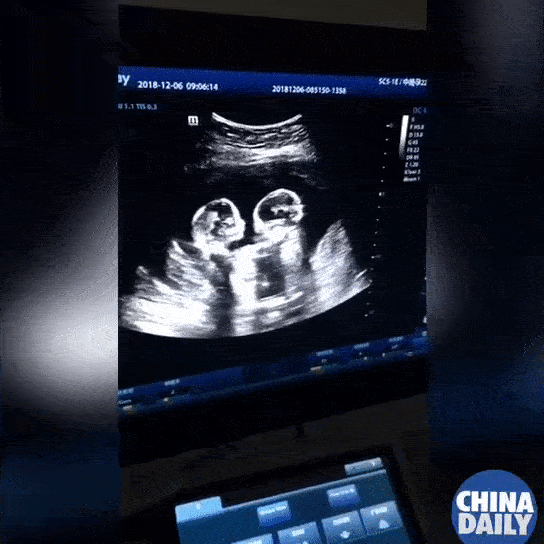

Mang thai 1 đứa trẻ đã mang đến rất nhiều niềm vui cho gia đình. Thế nên 1 cặp song sinh được ví như niềm hạnh phúc nhân đôi. Giống như một cặp đôi sống ở thành phố Ngân Xuyên, Trung Quốc, không chỉ chào đón 2 nàng công chúa xinh xắn mà sự khăng khít của 2 đứa trẻ thời còn nằm trong bụng mẹ còn khiến họ cảm thấy vô cùng ấm lòng. Đoạn clip ngắn ghi lại hình ảnh siêu âm thời điểm tháng thứ 4 của thai kỳ được chia sẻ cách đây không lâu đã gây bão mạng xã hội.

Theo China Daily đưa tin, đây là cặp song sinh đơn bào (hay còn gọi là Mo-mo) khi chúng chia sẻ cùng 1 túi ối và nhau thai trong bụng mẹ. Những trường hợp như vậy chỉ xảy ra với tỉ lệ cực kỳ nhỏ, khoảng 1/35.000-60.000 ca mang thai. Không chỉ là cặp song sinh hiếm lạ, cả 2 đứa trẻ còn sớm trở thành ngôi sao mạng xã hội khi chúng không thể chờ được đến lúc chào đời để tranh cãi với nhau. Ở tháng thứ 4 của thai kỳ, hình ảnh siêu âm cho thấy 2 bé như thể đang xảy ra mâu thuẫn, thậm chí quơ tay đánh nhau. Điều này dự báo nhiều khả năng chúng sẽ chí chóe với nhau cả ngày, bố mẹ nên chuẩn bị tinh thần.